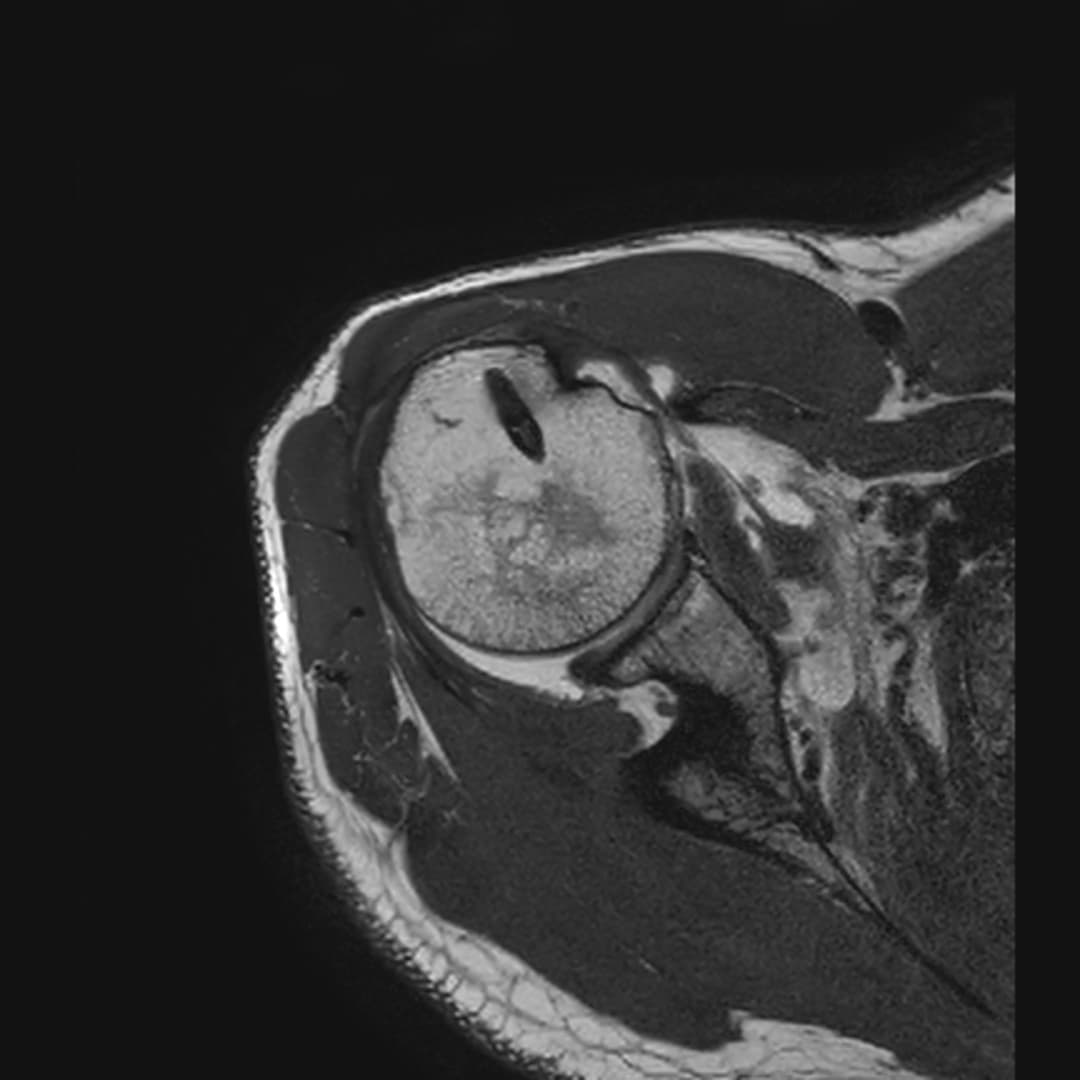

IRM

Ténodèse du long biceps intacte. Tendons sus et sous épineux respectés. Large diffusion du contraste depuis compartiment articulaire vers la BSAD.

Rupture du tendon sous-scapulaire avec rétraction grade II-III